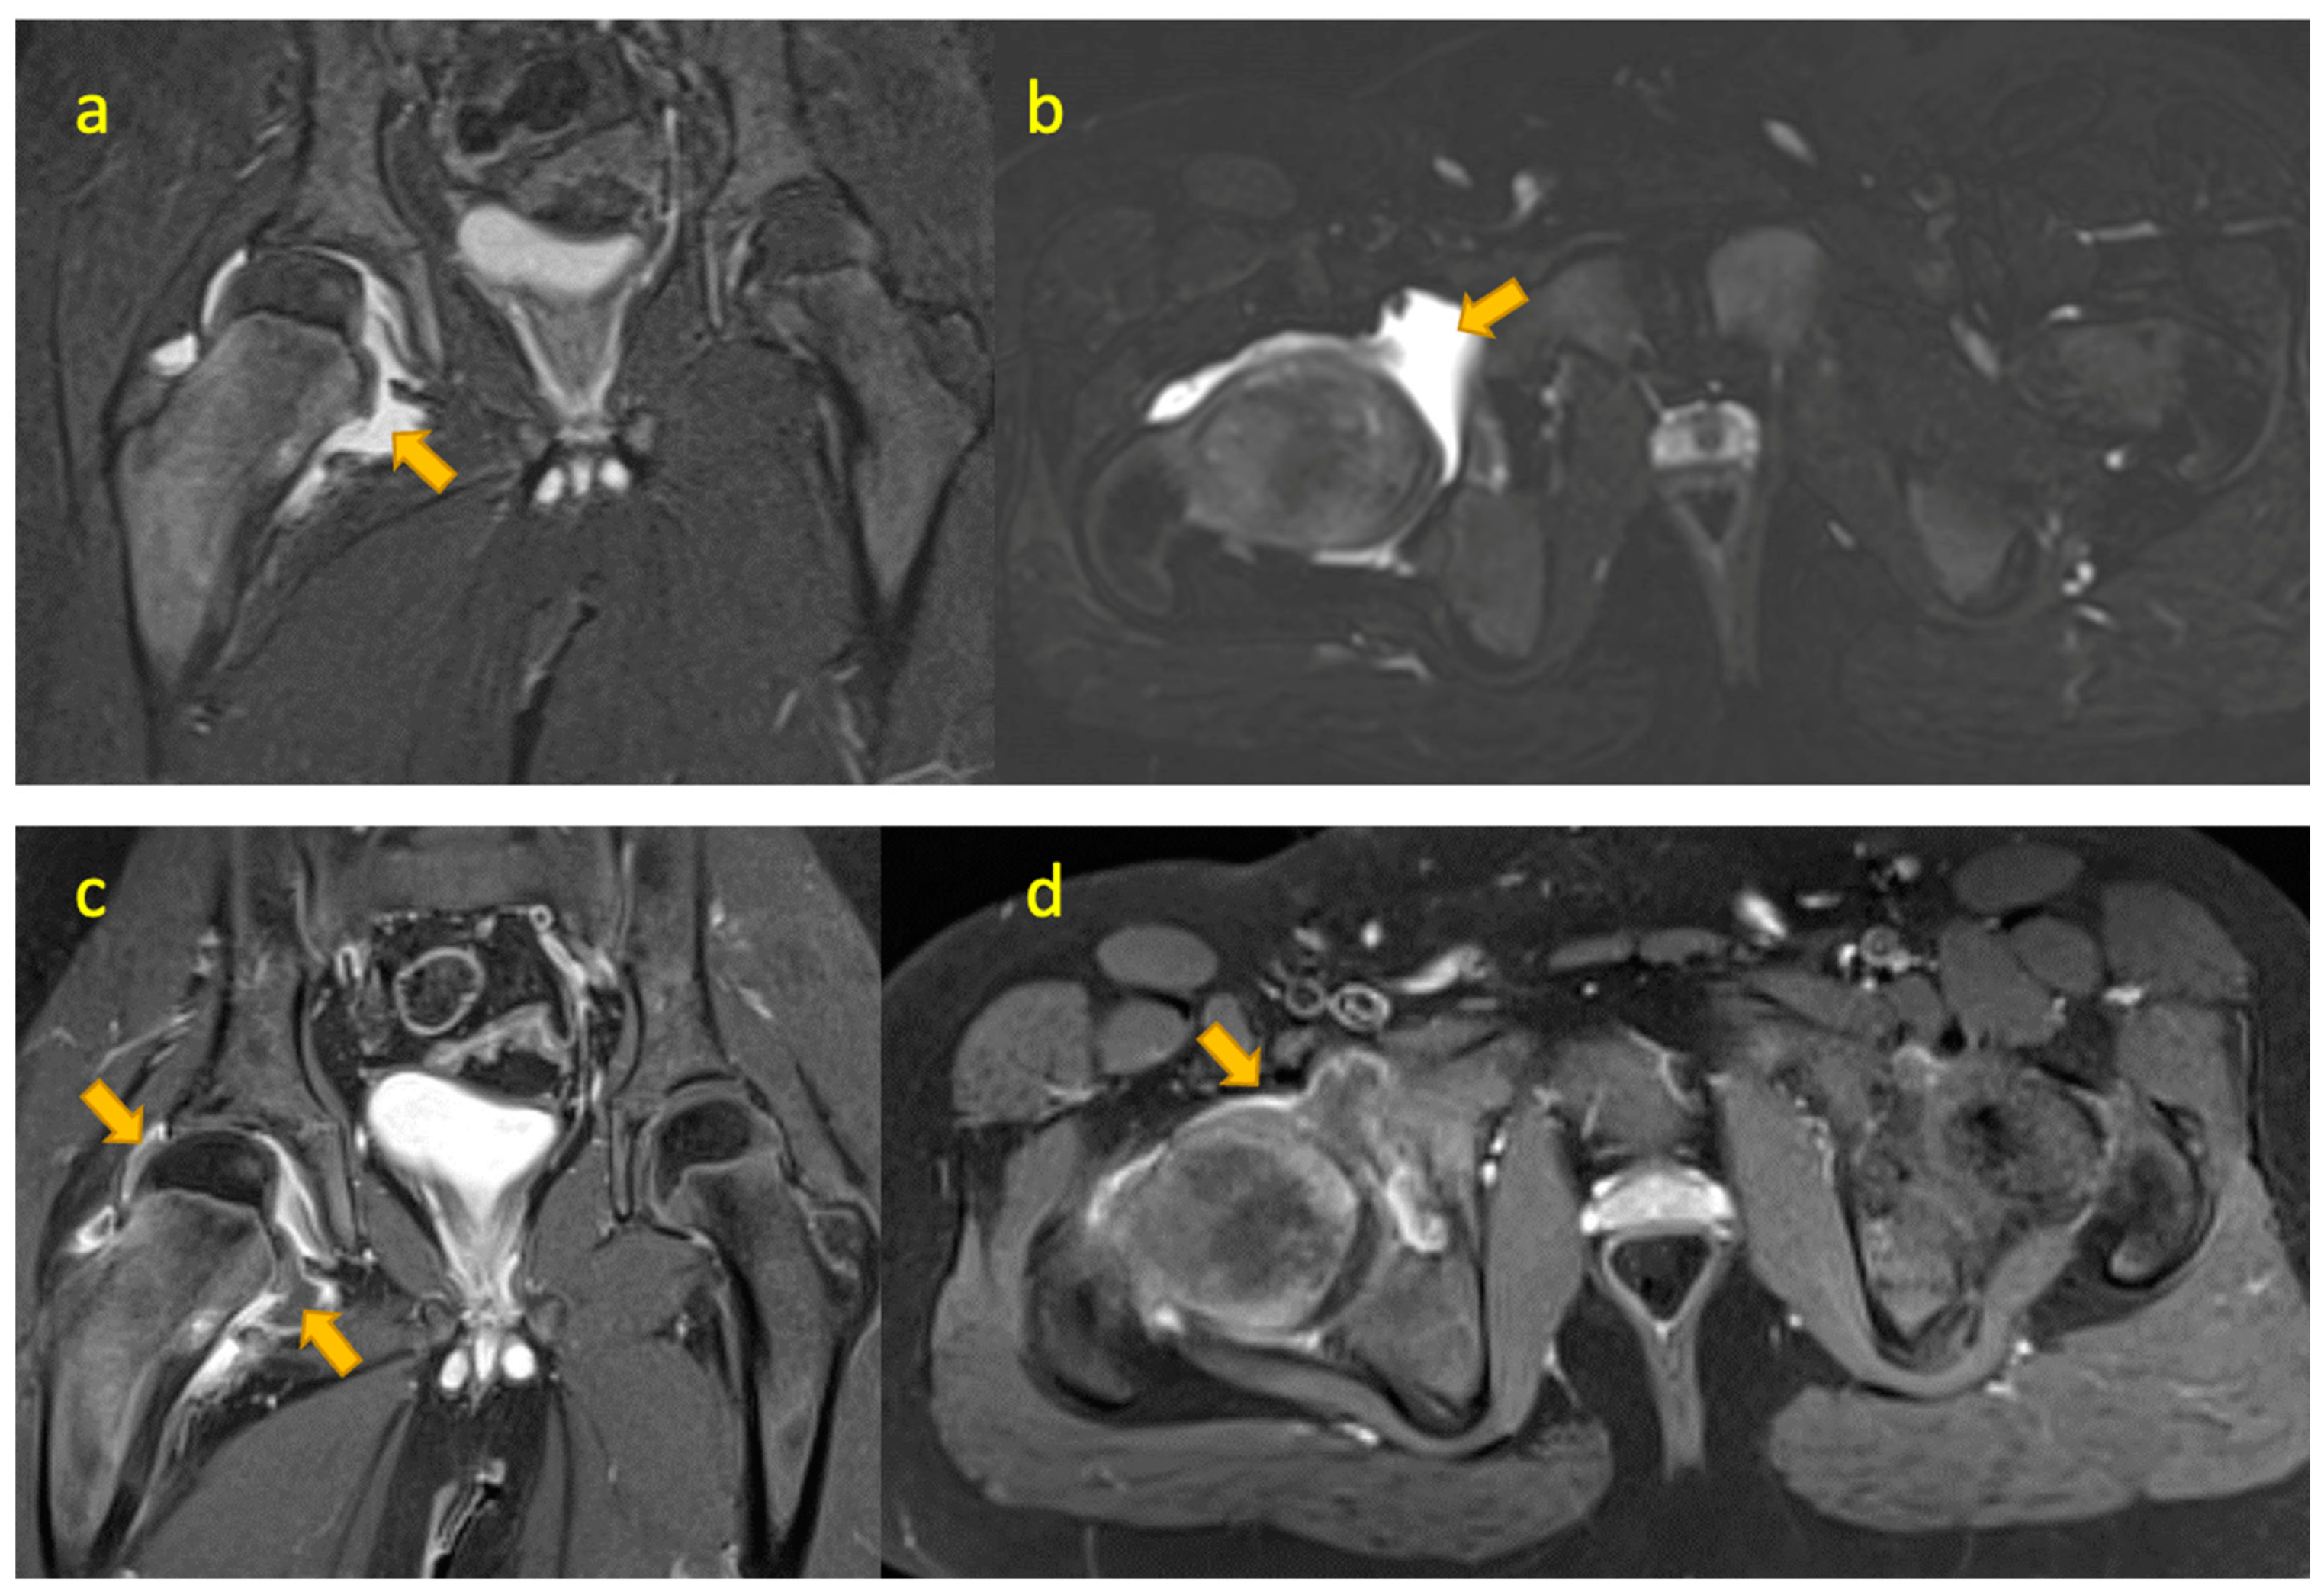

7. Crystal Arthritis of the Hip

15. TB(Tuberculous) Pyomyositis Thigh